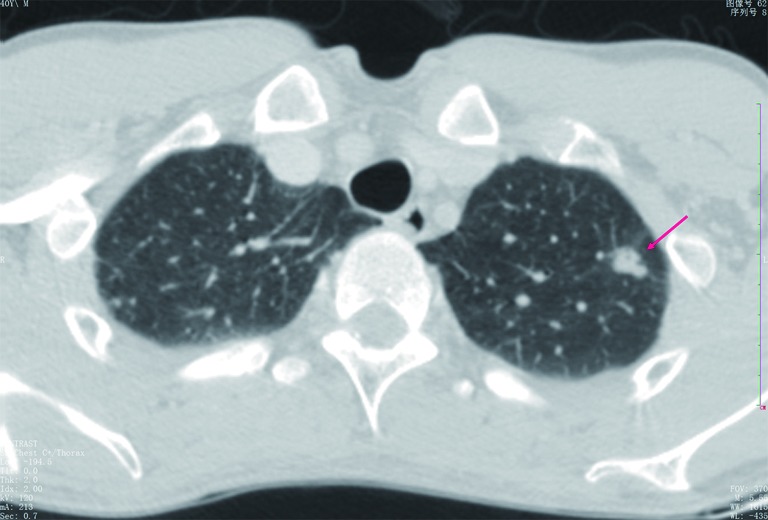

Figure 1.

CT shows a case of a small hamartoma (arrow) appearing as a non-calcification solid nodule with lobulated margin, mimics a malignant nodule.